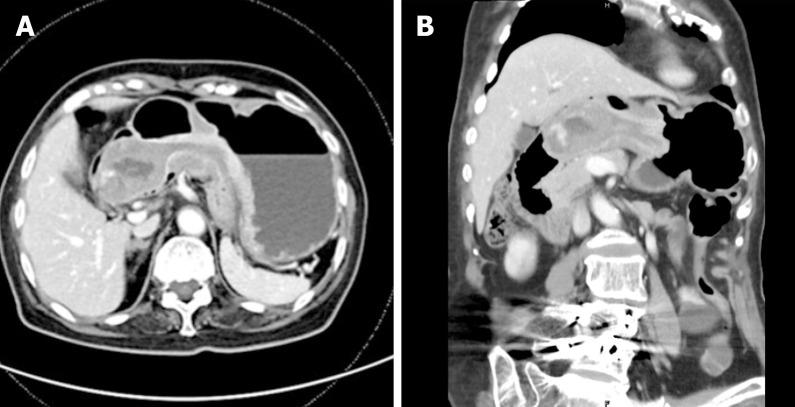

An 84-year-old woman presented with symptoms of postprandial fullness with nausea and occasional vomiting for a month. Initially, she visited a local clinic for help, where abdominal sonography revealed a space-occupying lesion around the liver, so she was referred to our hospital for further confirmation. Abdominal sonography was repeated, which revealed a mass with an alternating concentric echogenic lesion. Esophagogastroduodenoscopy (EGD) was performed under the initial impression of gastric cancer with central necrosis and showed a tortuous distortion of gastric folds down from the lesser curvature side to the duodenal bulb with stenosis of the gastric outlet. EGD was barely passed through to the 2nd portion of the duodenum and a friable ulcerated mass was found. Several differential diagnoses were suspected, including gastroduodenal intussusception, gastric cancer invasion to the duodenum, or pancreatic cancer with adherence to the gastric antrum and duodenum. Abdominal computed tomography for further evaluation was arranged and showed gastroduodenal intussusception with a long stalk polypoid mass 5.9 cm in the duodenal bulb. Under the impression of gastroduodenal intussusception, ESD was performed at the base of the gastroduodenal intussusception; unfortunately, a gastric perforation was found after complete resection was accomplished, so gastrorrhaphy was performed for the perforation and retrieval of the huge polypoid lesion. The gastric tumor was pathologically proved to be a GIST. After the operation, there was no digestive disturbance and the patient was discharged uneventfully on the 10th day following the operation.

一名84岁女性出现餐后饱胀、恶心及偶尔呕吐症状1个月。最初,她前往当地诊所求助,腹部超声检查发现肝脏周围有占位性病变,因此被转诊至我院进一步确诊。再次进行腹部超声检查,发现一个具有交替同心回声病变的肿块。在初步诊断为伴有中央坏死的胃癌的情况下进行了食管胃十二指肠镜检查(EGD),结果显示胃皱襞从胃小弯侧向十二指肠球部呈扭曲状向下延伸,胃出口狭窄。EGD勉强通过至十二指肠第二部,发现一个易碎的溃疡肿块。怀疑有多种鉴别诊断,包括胃十二指肠套叠、胃癌侵犯十二指肠或胰腺癌累及胃窦和十二指肠。安排了腹部计算机断层扫描进一步评估,结果显示胃十二指肠套叠,十二指肠球部有一个长蒂息肉样肿块,大小为5.9 cm。在胃十二指肠套叠的诊断下,在胃十二指肠套叠的基部进行了ESD;不幸的是,在完成完全切除后发现胃穿孔,因此对穿孔进行了胃缝合术并取出了巨大的息肉样病变。胃肿瘤经病理证实为GIST。术后无消化功能障碍,患者术后第10天顺利出院。